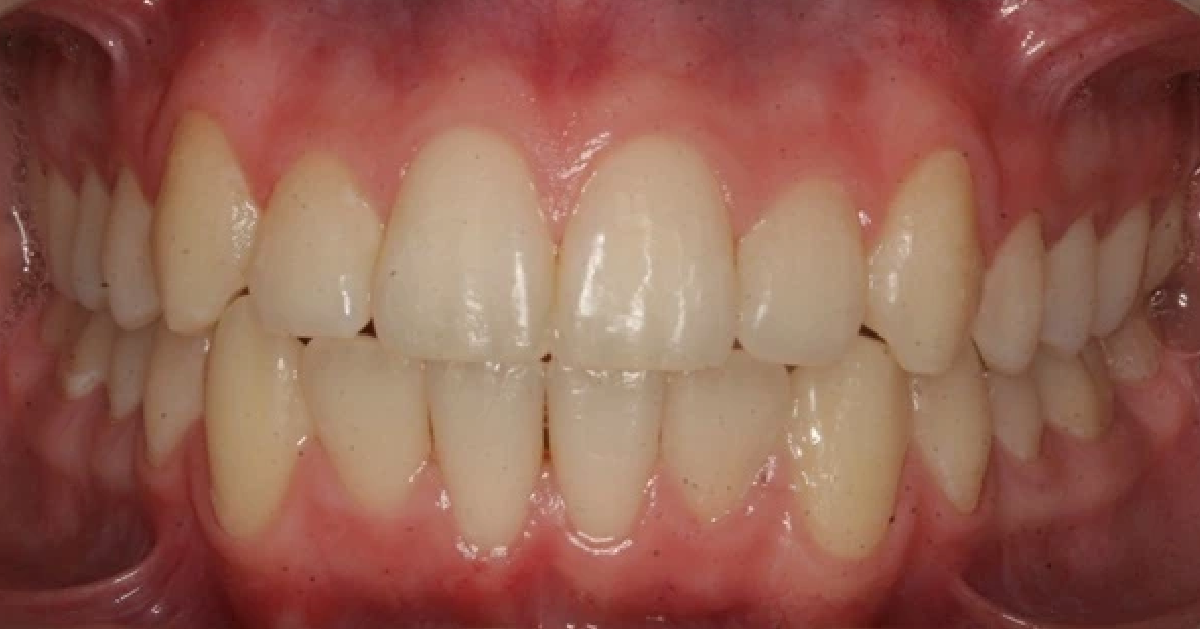

Vårt arbeid

Alle pasienter som vises har gitt skriftlig samtykke til at bildene kan brukes på klinikkens nettside.